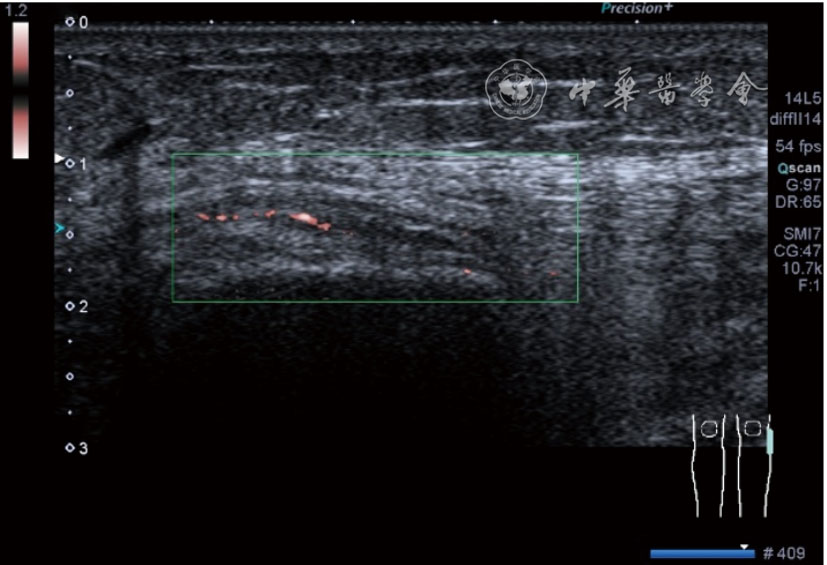

4.腓总神经分支卡压的治疗。常见腓浅神经、腓深神经感觉支卡压。主要表现为足背侧的感觉减退。腓深神经只支配第一、二足趾之间的感觉,腓浅神经支配的感觉区域较多,第一、二足趾之间外的足背感觉均由腓浅神经支配,根据感觉障碍区域确定卡压神经,超声可以明确卡压部位和原因。超声可显示卡压神经增粗,回声减低,局部软组织回声不均匀等(图4445)。治疗以液压松解药物注射为主。以腓深神经为例进行介绍。常见卡压部位在小腿和足背部。根据卡压部位不同,患者采取不同的体位。如果在小腿部采用平卧位,膝关节伸直位即可。穿刺区域常规消毒,探头涂抹耦合剂后套入无菌手套碘伏消毒或使用无菌耦合剂。将探头置于患者皮肤表面,小腿部位采用短轴扫查,确定神经卡压最明显的部位后,用一次性5 ml注射器,应用25G注射针头抽吸0.5%利多卡因4 ml+地塞米松3 mg平面内进针到达神经周围,注意回抽无血液回流后进行注射(图46),完成注射松解,拔出针头,局部压迫3分钟,创可贴覆盖。如果在足背部可以采取平卧位,屈髋、屈膝将足平放于治疗床面。治疗前准备同小腿部,采用长轴显示神经,确定神经卡压最明显的部位后,用一次性5 ml注射器,应用25G注射针头抽吸0.5%利多卡因2 ml+地塞米松1 mg平面内进针到达神经表面进行注射(图47),完成注射松解,拔出针头,局部压迫3分钟,创可贴覆盖。

图44 腓浅神经在小腿中下1/3筋膜穿出部位卡压的短轴和长轴超声图像

图45 腓浅神经在小腿中下1/3筋膜穿出部位局部软组织回声不均匀超声图像